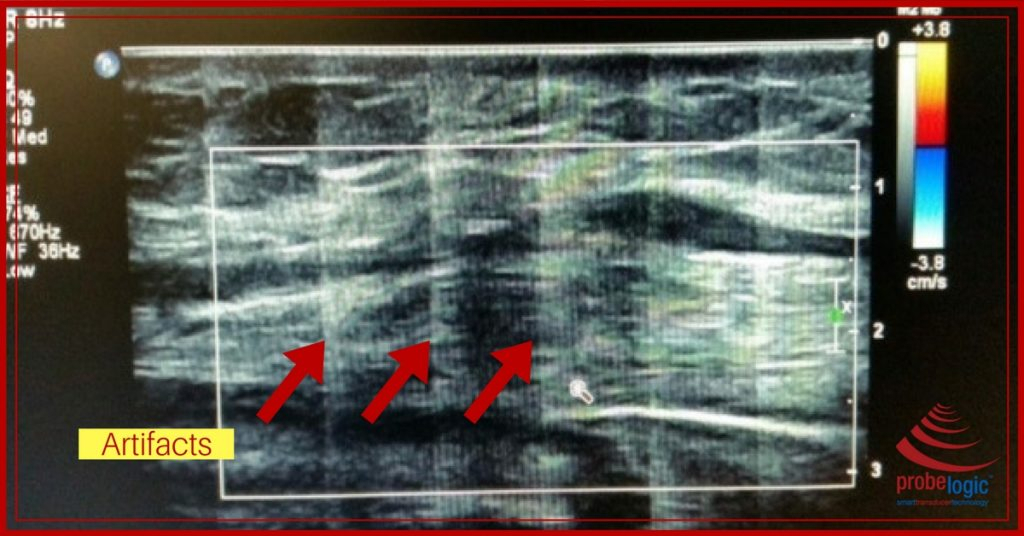

1. Artifacts on the screen

– we see this happening when the cable gets run over by the machine. It damages the internal shielding and causes the artifacts you are seeing in the picture below to appear. If you are seeing something like this on your screen, you really need to get this checked.